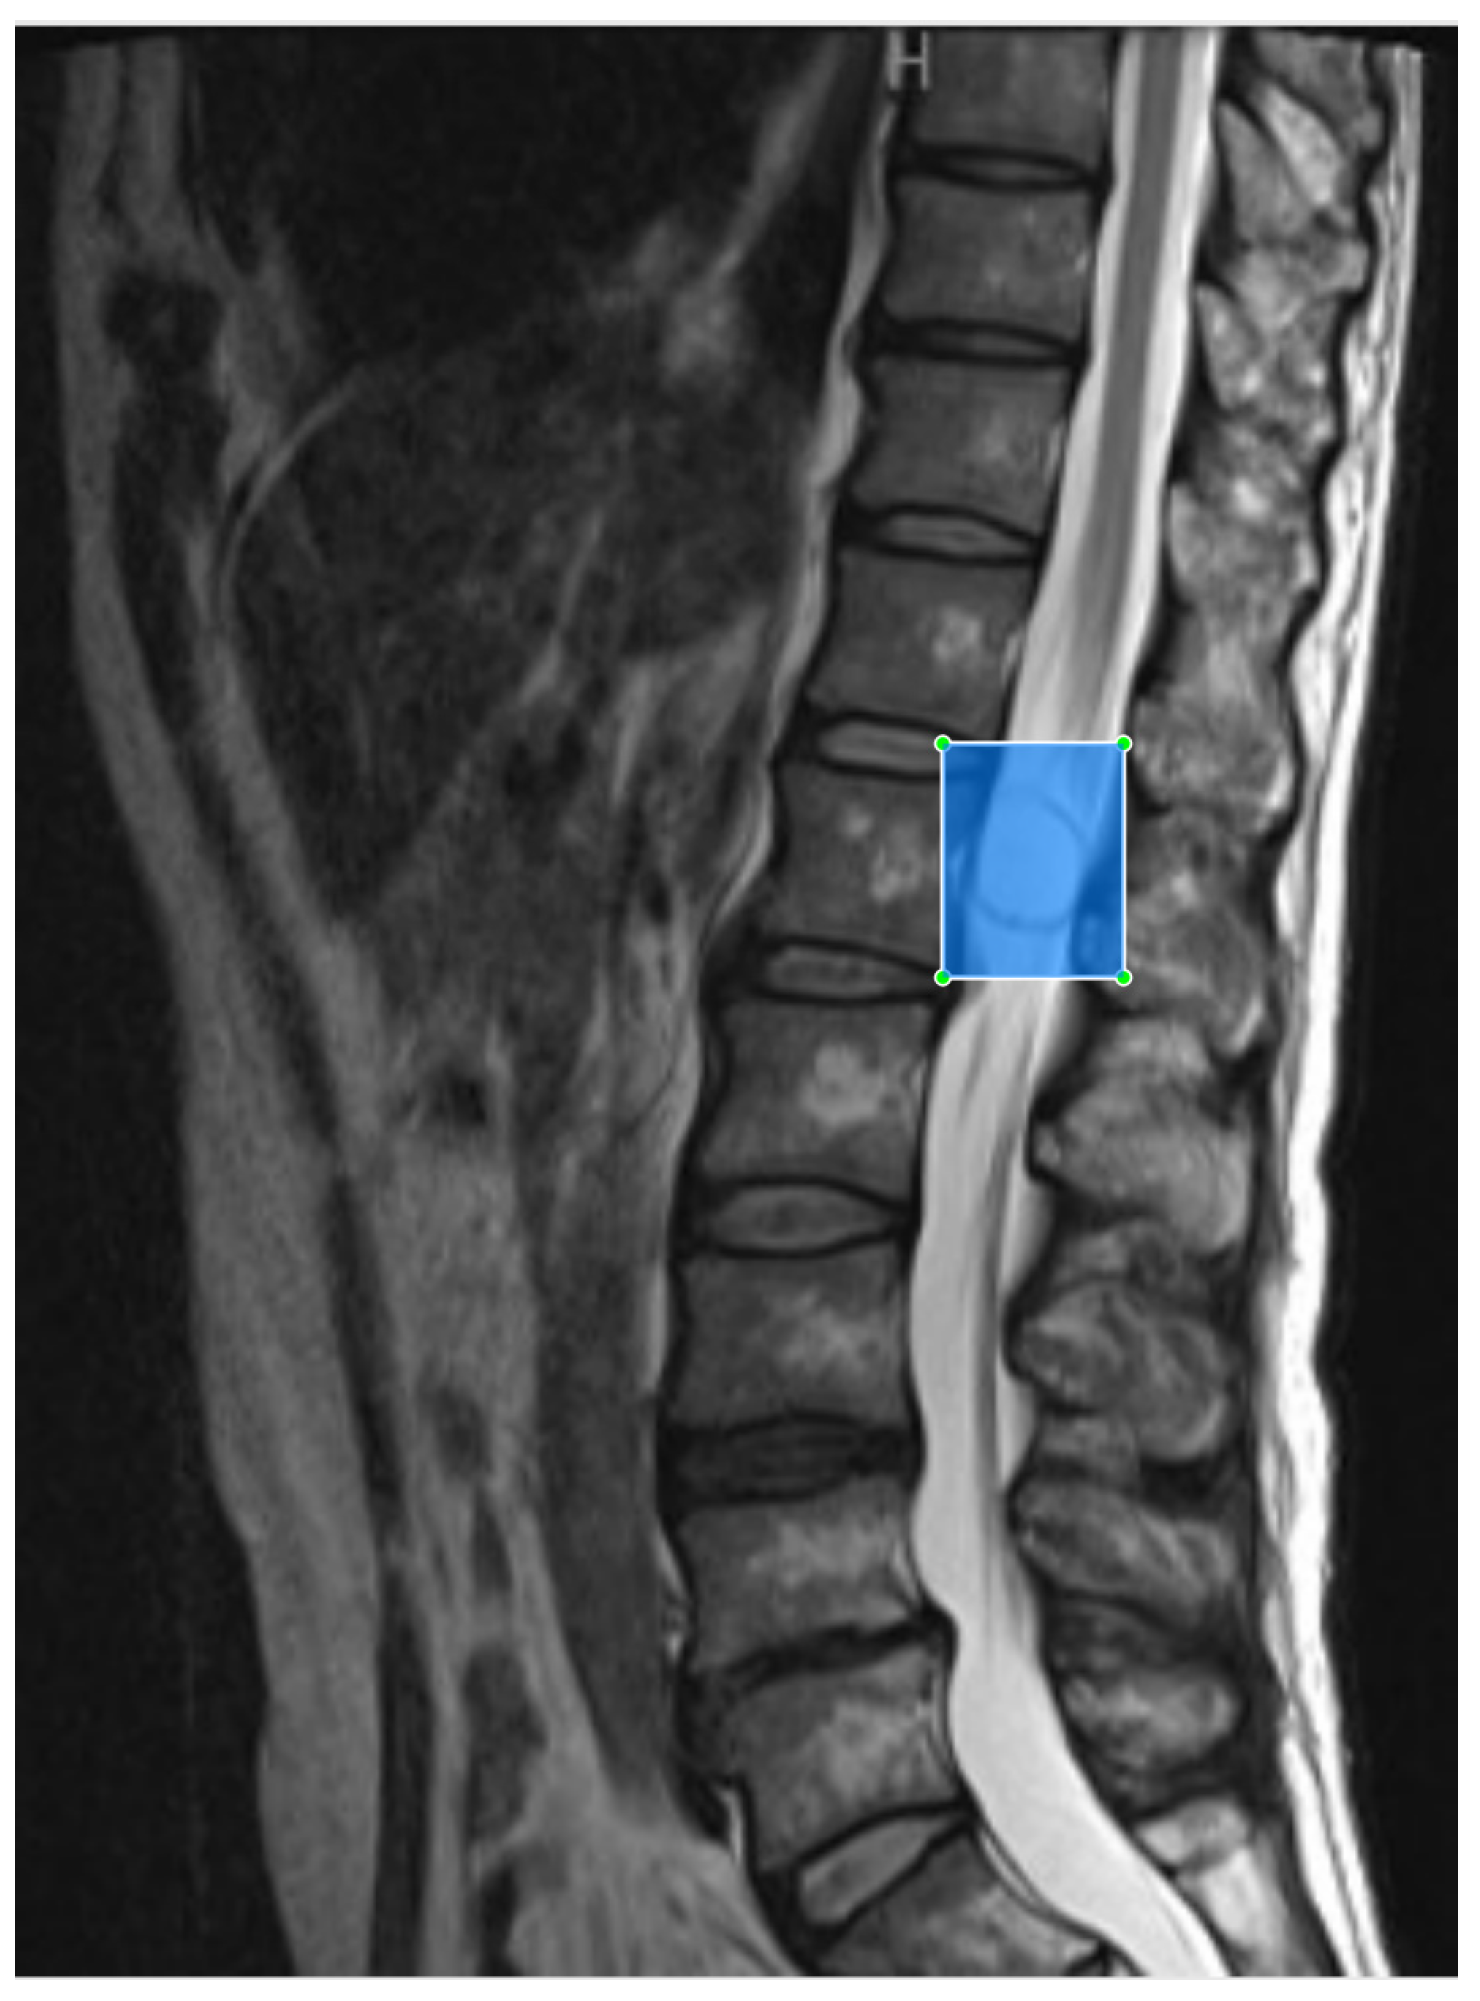

Spinal MRI scans from Digital Imaging and Communications in Medicine files were exported using the JPEG format from the picture archiving and communication systems at our hospital. Images were annotated using a label image [23] by manually inputting a minimal bounding box containing the tumor completely and anteroposterior border of the spinal canal on sagittal MRI to generate an image for object detection training (Figure 2). Schwannoma was labeled sch and meningioma was labeled men. To ensure that the tumor was recognized, we selected several slices of the tumor (1–4 slices, depending on the case). Two slices of each control were selected. The images were trained after pixel value normalization, which replaces pixel values with real values between 0 and 1.

Figure 2. Preparation of images for training the object detection model. Tumor recognition slices were selected and placed within a minimal bounding box on the sagittal plane during magnetic resonance imaging.